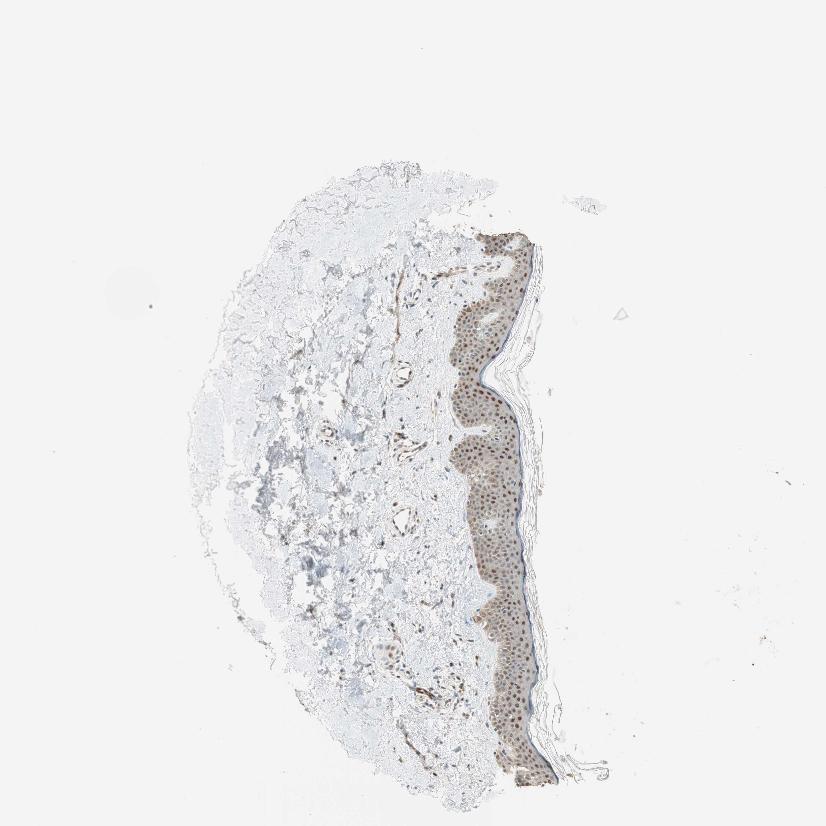

SKIN 1 - Antibody stainingi

Antibody staining in the annotated cell types in the current human tissue is reported as not detected, low, medium, or high, based on conventional immunohistochemistry profiling in selected tissues. This score is based on the combination of the staining intensity and fraction of stained cells.

Each image is clickable and will lead to virtual microscopy that enables deeper exploration of all samples and also displays staining intensity scores, fraction scores and subcellular localization as well as patient and tissue information for each sample.

Antibody HPA008399Antibody HPA017017Antibody CAB015221

Langerhans LowMediumLow

Fibroblasts LowNot detectedMedium

Keratinocytes MediumMediumLow

Melanocytes MediumNot detectedLow